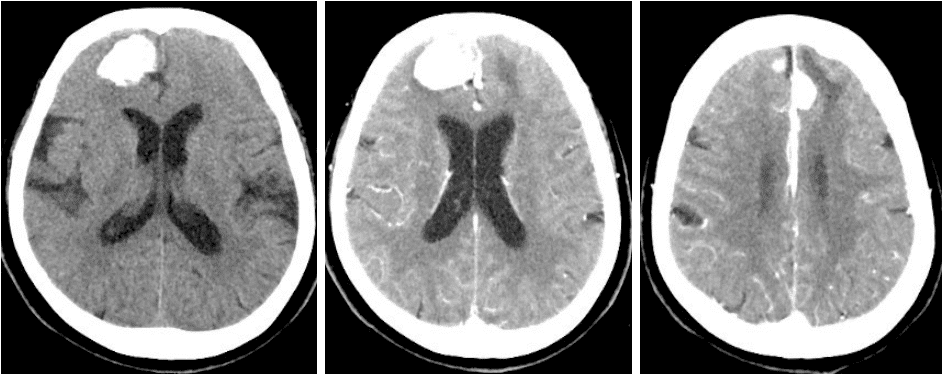

头CT平扫+增强(2024-11-26)右侧额部可见一椭圆形高密度影,截面约3.3×2.3cm,增强扫描局部可见强化。左侧额部可见一类圆形明显强化影,直径约1.6cm。脑室及脑池系统无扩张。双侧脑沟裂无增宽、加深,中线结构居中。